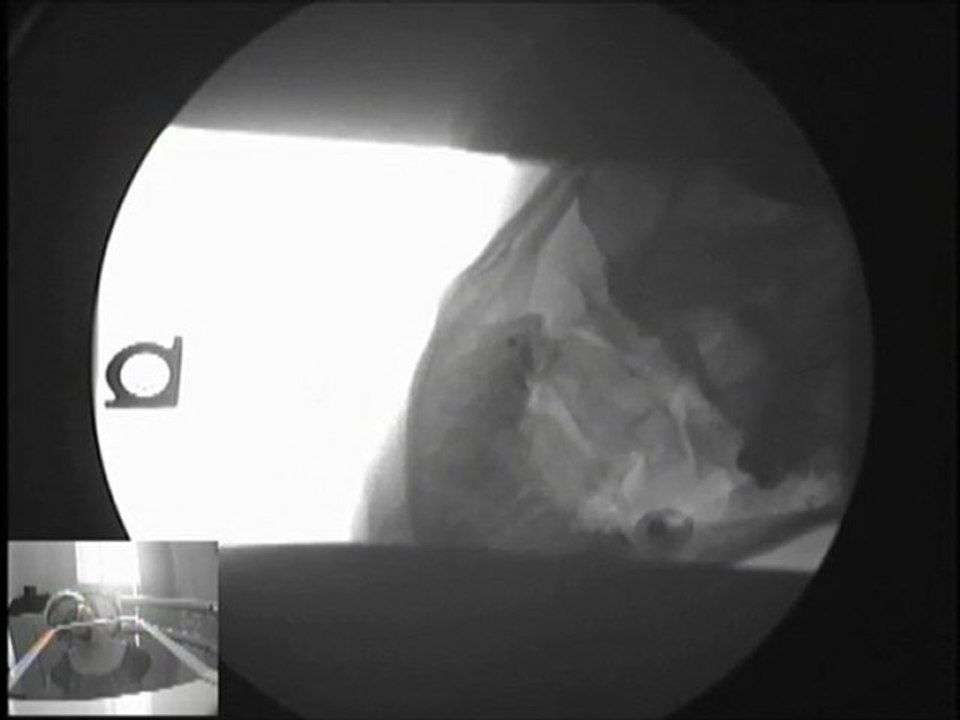

Treatment for Whiplash and After Car Accident Injuries

http://chiropractormissouri.com Chiropractor in Springfield MO talks about treatment for whiplash and after car accident injuries. Learn how chiropractic can treat these conditions. Call 417-831-0976 now.